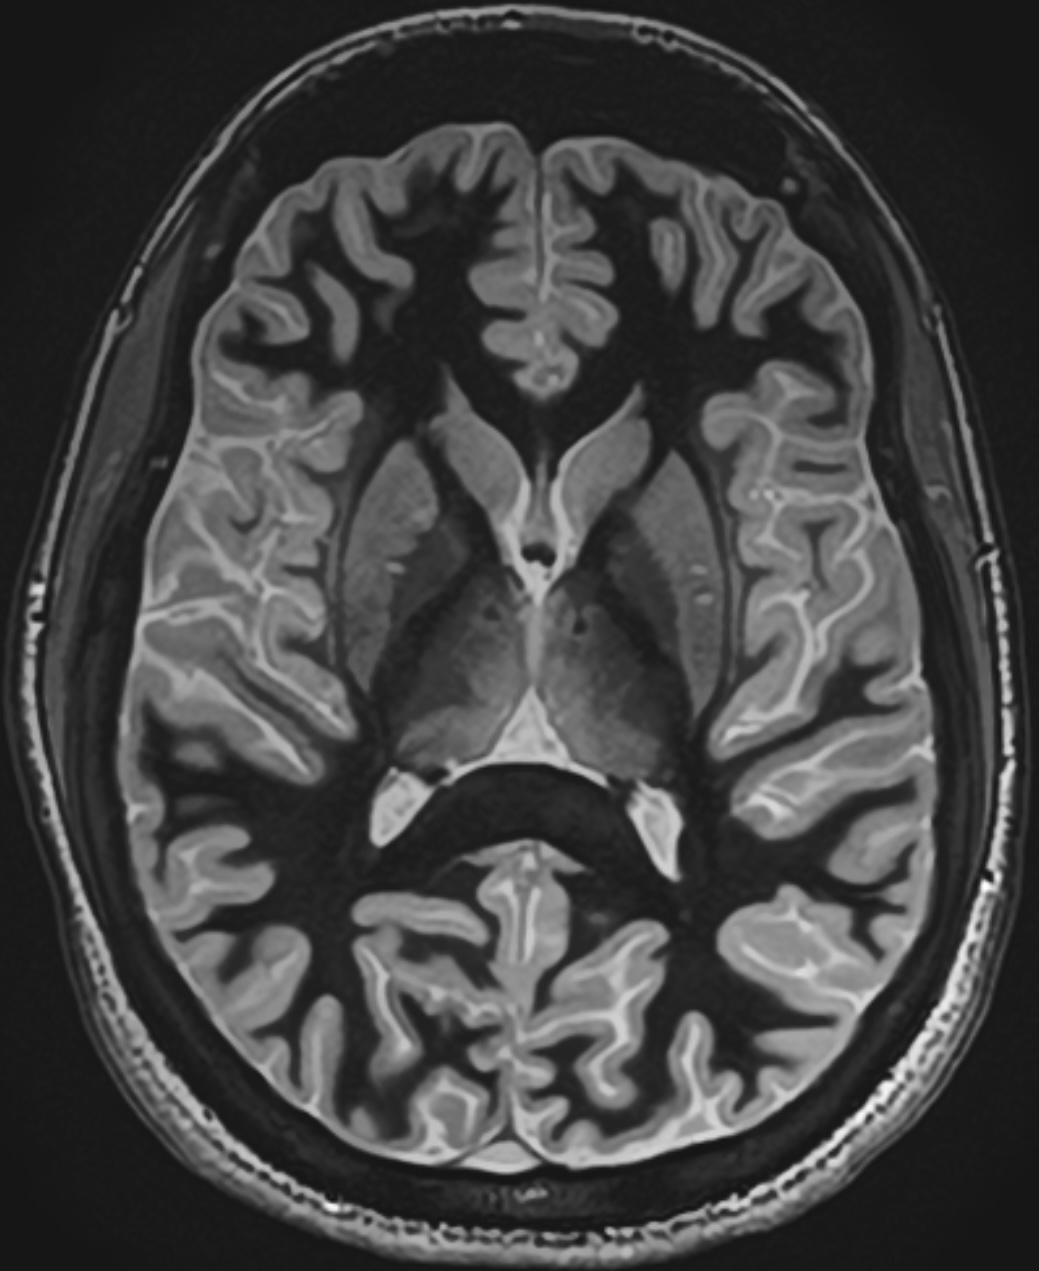

Image : WMn MPRAGE, séquence développée par Thomas Tourdias pour le thalamus. Crédits photo, Thomas Tourdias et Fanny Munsch